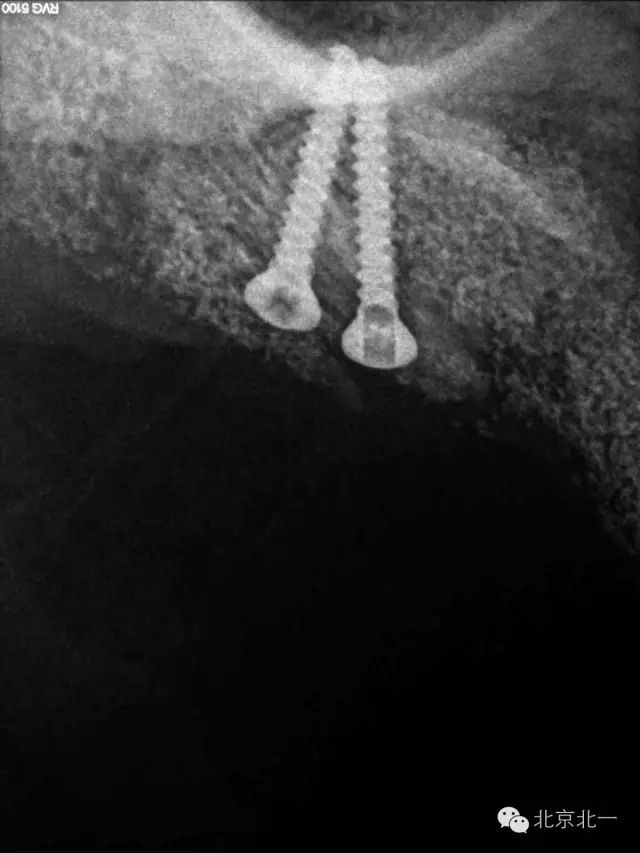

圖十七:縫合。非潛入

圖二十三:種植后當(dāng)天全景片。

圖十六:植入植體

圖七:骨塊堅強內(nèi)固定